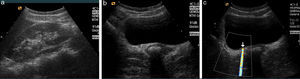

Calculi are identified as hyperechoic focuses with a posterior acoustic shadow. Small lithiases (<5mm) or those located in the middle ureter are especially difficult to see. That explains the wide variation (47.5–98%) in the sensitivity of the ultrasound.38–40 Another limitation of ultrasounds is that several hours must pass until the dilation of the excretory duct; so it can be negative in the initial stage of RC if lithiasis is not identified. The correct hydration of the patient before the proceeding provokes the distension of excretory duct and the adequate filling of the urinary bladder improving the view of the distal ureter.40,41 Combining the “B-mode” with the color and pulsated Doppler methods increases diagnostic yield thanks to other suspicious signs such as twinkling or comet-tail artifact (Fig. 2) of the Doppler color ultrasound allowing us to detect small lithiases that do not get to generate a posterior shadow.42–44 A reduced or asymmetrical ureteral jet and especially the lack of it are also suspicious signs of ureteral obstruction.45 The high intrarenal resistance index (RI) is used as a differential criterion between obstructive and non-obstructive dilation in such a way that >0.7 RI or a difference >10% between the two kidneys is considered diagnostic of obstructive uropathy.46 However, the variability of RI normal values with a trend to increase with age, systolic pressure and decrease of renal function, should be considered.47

Ultrasound of a patient with right RC. (a) Right kidney with minimal ectasia of some calyces–almost indiscernible without other findings. (b) Around the right meatus there is a dubious ureteral lithiasis without evident dilation. (c) Color Doppler. “Twinkling” artifact that helps identify ureteral lithiasis. This artifact occurs in coarse and irregular interfaces reflecting ultrasound waves intensely. It is a rapid alternation of several colors that appear right behind a hyperechogenic image giving the false appearance of movement.